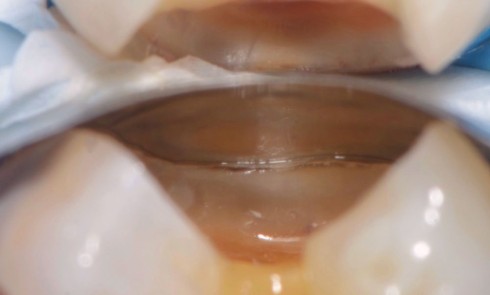

En odontologie prothétique, l’empreinte représente une étape cruciale, souvent délicate, dont dépendra directement la qualité de la prothèse. En 1979,...